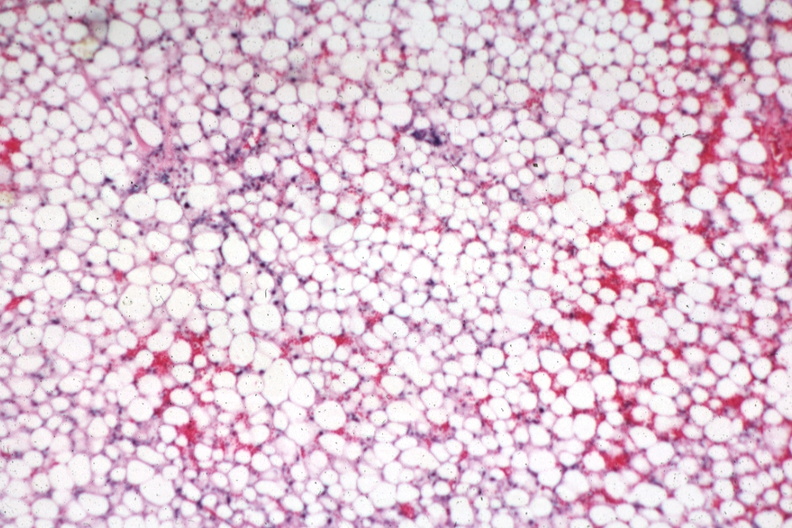

HISTOLOGY: HEPATOBILIARY: LIVER: BILIARY: Fatty Change: Micro low mag H&E looks like adipose tissue

- biliary, fatty change, hepatobiliary, histology, liver